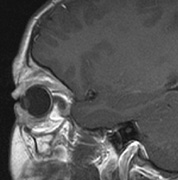

CNS hemangiomas are the most common tumor of VHL, affecting 60% to 80%, with a predilection for the cerebellum and spinal chord. An enlarging cystic component is a frequent finding in symptomatic tumors. Patients typically present in their early 30s; headaches or neck pain in affected individuals should not be ignored.172,173 On microscopy, CNS hemangiomas resemble retinal capillary hemangiomas. Their malignant potential is low.174 The treatment is surgical (Fig. 17, A and B).13

Fig. 17. Images from a 13-year-old boy with Von Hippel-Lindau syndrome. (a) Coronal postcontrast T1-weighted imaging reveals a cystic lesion with an enhancing nodule at the pial surface typical of a hemangioblastoma. (b) A second solid enhancing hemangioblastoma is seen at the craniocervial junction on a sagittal postcontrast T1-weighted image. (c) Associated cystic lesions (arrows) are seen within the pancreas.